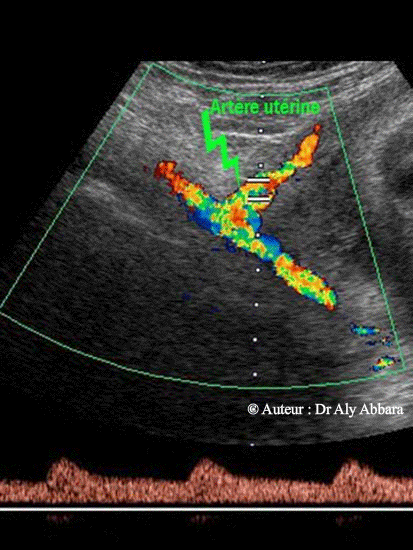

Images échographiques comparant le spectre normal de l'artère utérine et celui de l'artère iliaque externe

Image comparant l'aspect du spectre normal de l'artère utérine droite immédiatement après son croisement avec l'artère iliaque externe droite et spectre cette dernière.